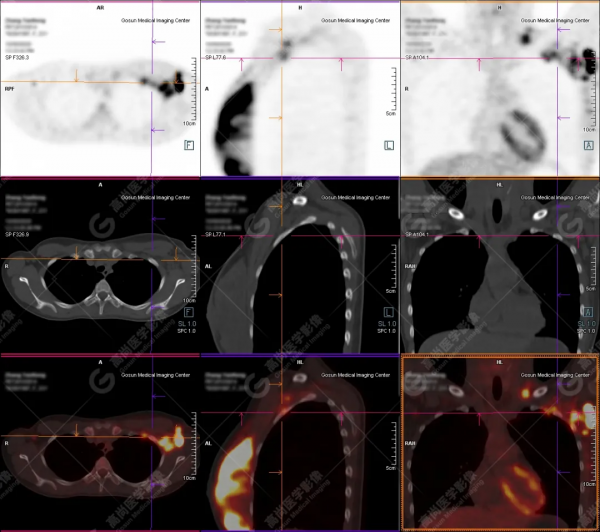

病例一

病史:患者23歲,年輕女性。

發現乳腺結節半年,近一月自覺有增大、伴疼痛,來院就診。

腫瘤標誌物CA199:59.0,HCG、CA125、724、153、CEA均正常。

未行B超檢查。

既往經期正常,餘無特殊。

今早行本院MR+增強,提示乳腺多發佔位,即時行PET/CT檢查。

檢查所見:

PET/CT提示:

左側乳腺內瀰漫片塊狀、結節狀高代謝病灶;

左側鎖骨上區、左側腋窩、左側胸壁肌間隙、雙側肺門及縱隔多發高代謝腫大淋巴結;

考慮為乳腺癌多發淋巴結轉移。

穿刺病理結果:

左側乳腺浸潤性導管癌,中低分化。